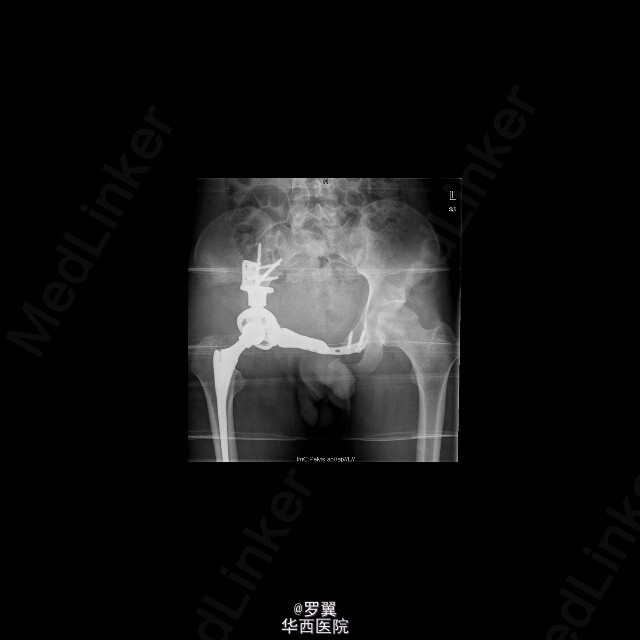

患者男,21岁,因“ 右髋疼痛7月伴右腹股沟包块2月”入院。查体:视:右腹股沟区可见一大小约15cmx10cm包块,未见浅表静脉怒张,无红肿及渗出,皮肤无破溃。触:质硬,边界不清,皮温稍高,局部深压痛。在右大腿根部前正中可扪及股动脉搏动。右侧鞍区感觉明显减退,右大腿上段内侧浅感觉减退。.肛门括约肌肌力Ⅲ级。动量:右髋伸90°,伸-10°。做伸直动作时患者包块区域疼痛加重。复查ct:盆腔巨大肿瘤,骨质破坏,考虑恶性肿瘤可能性大,核磁共振:考虑盆腔恶性肿瘤。入院后,完善相关辅助检查及术前准备,并采用阿霉素化疗方案化疗后,后在全麻下行腹主动脉球囊阻断下右侧骨盆肿瘤切除、腹股沟淋巴结清扫、人工组配式半骨盆置换术。术后1周即能拄拐下地,右髋能屈曲50°,右膝能屈曲65°。现出院。